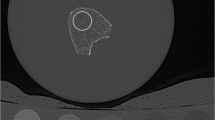

All acquired images were transferred to a remote LINUX workstation. An in-house developed algorithm based on IDL (Interactive Data Language, Research Systems, Bolder, CO, USA) was used for image analysis. The MDCT and HR-pQCT images of each functional spinal segment unit were opened in separate image panels at the same time. The operator identified visually the slice of the middle vertebra equidistant to its endplates in the MDCT and HR-pQCT images. Subsequently, the 20 and 150 most central slices of the middle vertebra were selected in the MDCT and HR-pQCT images, respectively. Twenty oval regions of interest (ROIs) were manually placed at once in the ventral half of the middle vertebra of the functional spinal segment unit in the selected slices of the MDCT images by using a batch process. The placement of the ROIs was similarly performed in the selected 150 slices of the HR-pQCT images. The operator matched the position of ROIs in MDCT and HR-pQCT images visually in the simultaneously opened image panels. Dependent on the vertebral level of the functional spinal segment units, the size of oval ROI was adjusted accordingly with a length varying between 24 and 35 mm and a width varying between 15 and 26 mm. The length and width of the oval ROIs were identical in corresponding MDCT and HR-pQCT images of each functional spinal segment. Standard QCT-derived BMD measurements are usually performed in a 8–10 mm slice in L1–L3 covering the central third of the vertebral height [8]. Since the functional spinal segment units were in the majority harvested from the thoracic spine, we decided to reduce the height of the ROIs to about 6 mm (i.e., 20 and 150 slices of the MDCT and HR-pQCT images, respectively) to account for smaller heights of the thoracic vertebrae. In addition, ROIs were drawn in two phases of the Mindways calibration phantom in the MDCT images (Fig. 3).

Representative MDCT image of the functional spinal segment unit: an oval region of interest (ROI) was placed in the ventral half of the middle vertebra of the functional spinal segment unit. In addition, ROIs were drawn in two phases of the Mindways calibration phantom in the MDCT images. The ROIs were positioned in the 20 most central slices of the middle vertebra in the MDCT images and correspondingly in the 150 most central slices of the middle vertebra in the HR-pQCT images